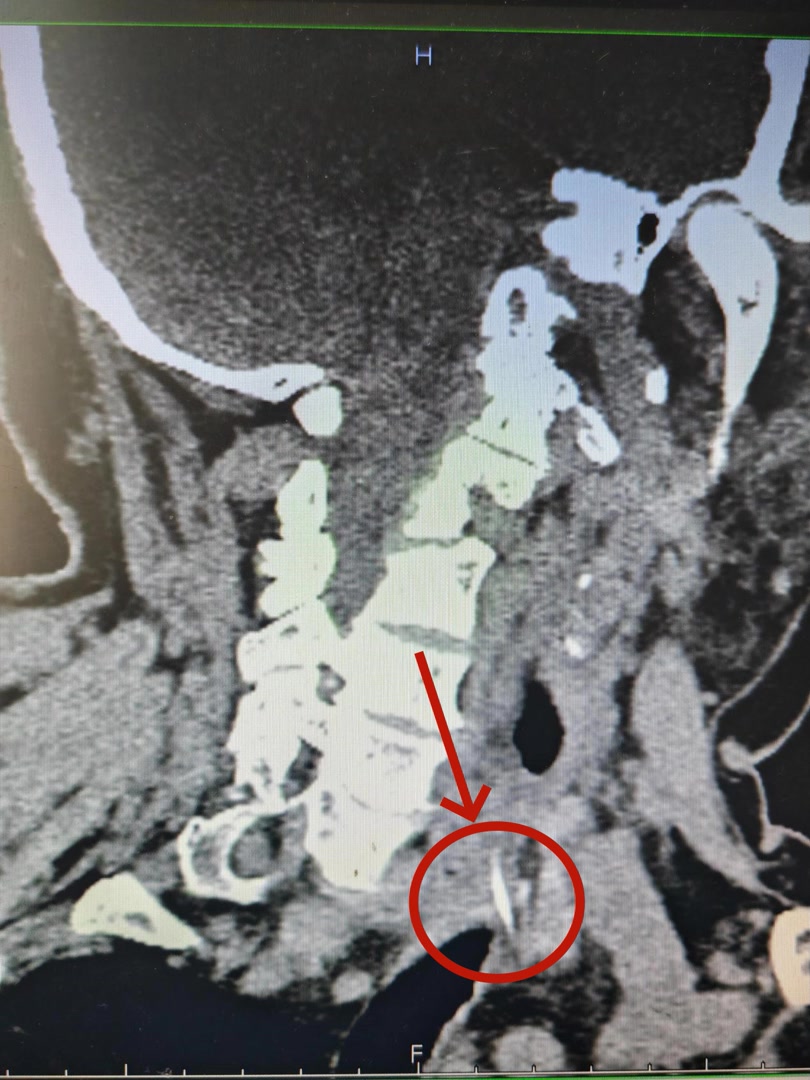

“喉咙疼,像针扎一样,咽口水都费劲。”这名患者因误吞鱼刺后喉咙剧痛、吞咽困难,到北京友谊医院就诊。医生检查发现,这根长约2.5厘米的鱼刺已穿透食管壁,可能引发严重感染、刺破颈部大血管等致命风险。该院团队为患者实施了手术,将鱼刺完整取出。患者已顺利康复。